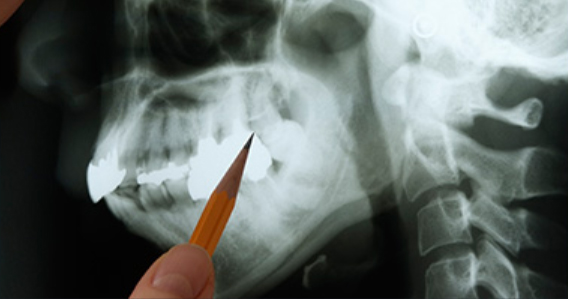

매복된 사랑니는 3D 첨단 CT촬영으로 상태를 정밀검사하고 발치계획을 세웁니다.

사랑니 발치 시에는 뿌리가 신경관과 근접해 있는지 또 어느쪽으로 휘어져 있는지를

파악해야 훨씬 더 안전하고 편하게

또 빠르게 뽑을 수 있습니다.

최첨단 3차원 CT를 이용하여 사랑니 뿌리의 위치와

신경관 위치 등을 정밀하게 분석한 후 시행하고 있습니다.